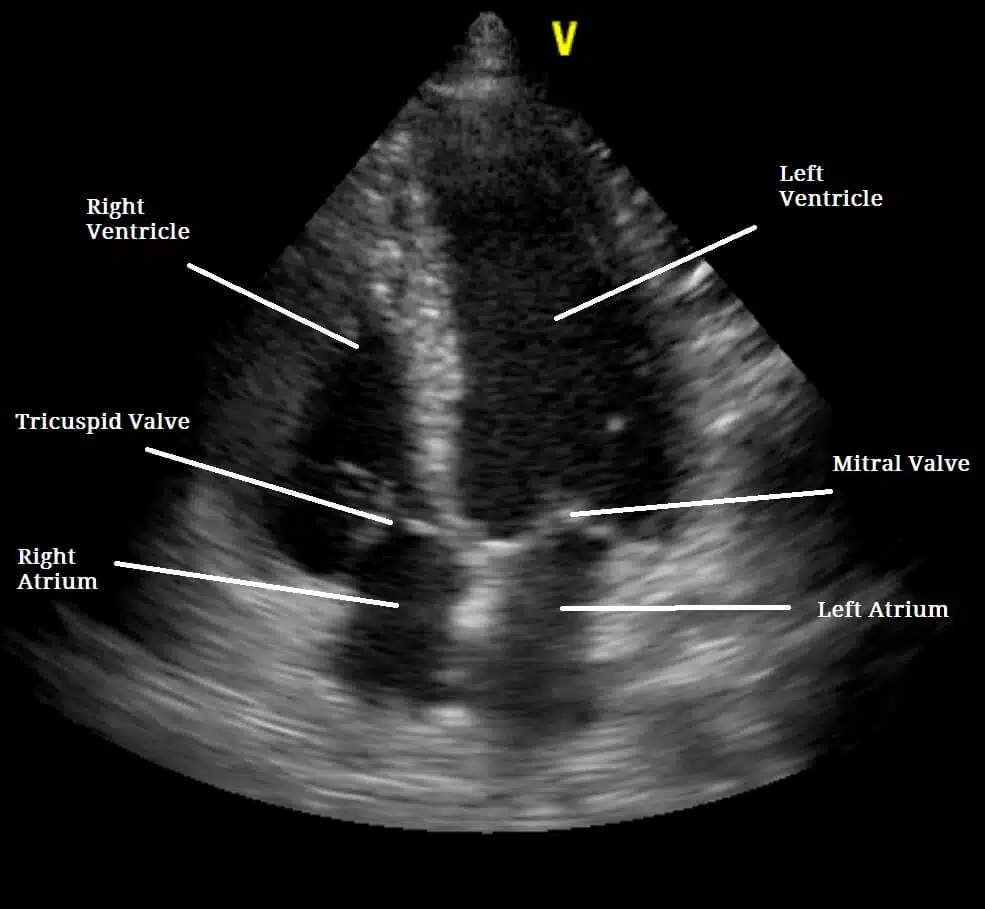

تخطيط صدى القلب ، والمعروف أيضاً باسم إيكو القلب ، هو فحص غير مؤلم يستخدم لتشخيص تشوهات القلب مثل تلف أنسجة القلب بسبب النوبة القلبية، أو ضعف أداء صمامات القلب. يستخدم تخطيط صدى القلب ( إيكو القلب ) الموجات فوق صوتية لتصوير القلب ، وتردد هذه الموجات لصدى القلب. يمكنهم عرض شكل وحجم وحركة الأذينين والبطينين والصمامات في القلب. يمكن أن يُظهر تخطيط صدى القلب أيضًا تدفق الدم عبر القلب.